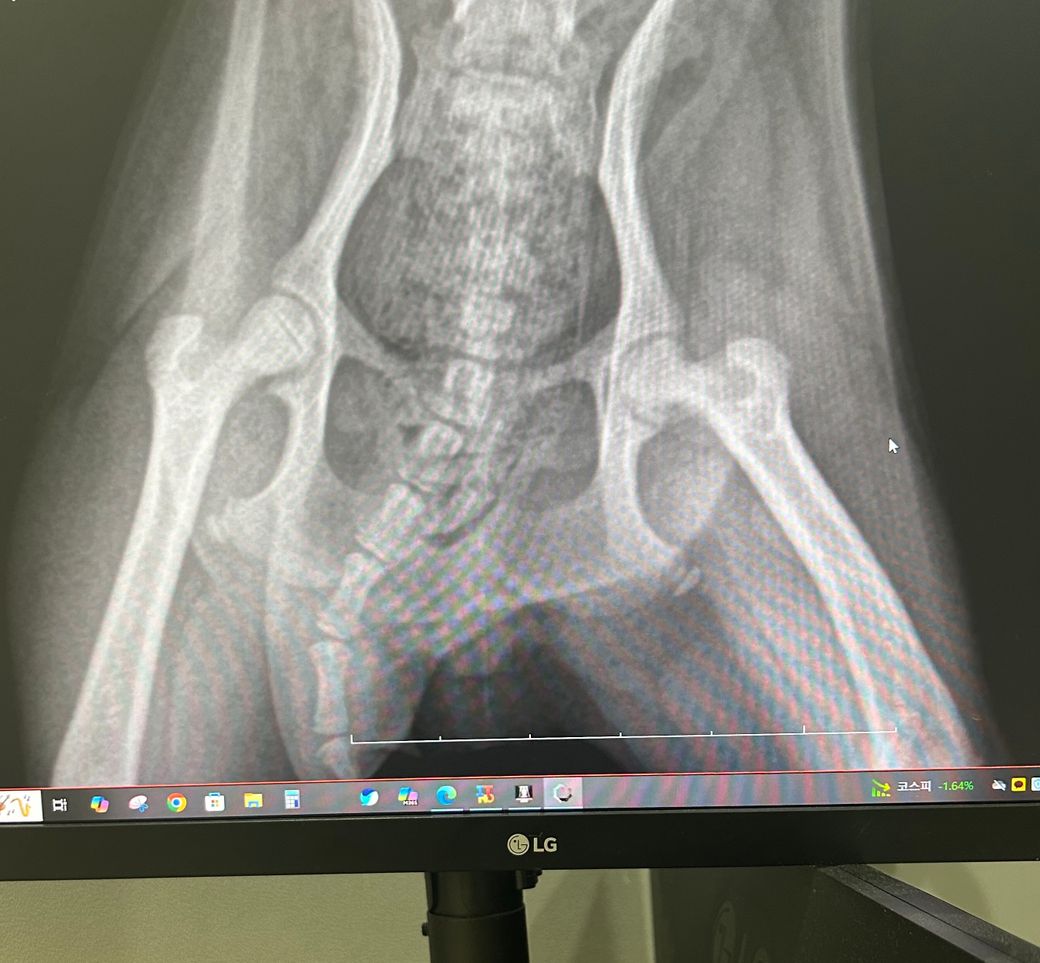

강아지 무혈성괴사 LCPD 엑스레이좀 봐주세요

어제부터 갑자기 한쪽 다리를 절어서 오늘 엑스레이 찍어봤어요

무혈성괴사 의심된다는

소견을 받았는데

말그대로 의심이라 ㅠ 수술얘기가 없으셨는데

사진으로 봐서는 아직 극초기인가요?

의심되는 수준의 사진인건 옳습니다. 통상 1주일 경과후에 방사선 재촬영을 해보면 확진 가능합니다.